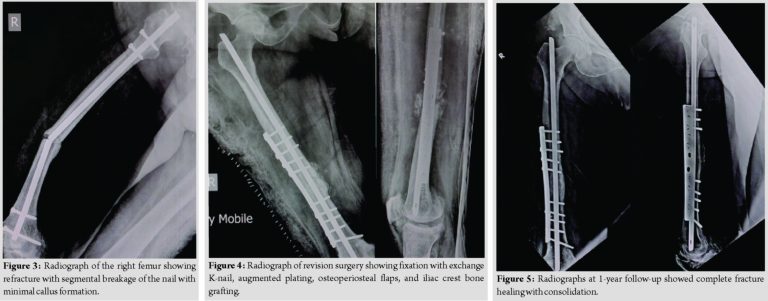

The radiographs at 3months showed evidence of callus formation, and the patient was advised weight-bearing walking. Subsequent radiographs at follow-ups showed slow healing of the fracture with minimal callus formation. At 9 months, the patient again presented to the emergency room with thigh pain after getting up from sitting position. Clinical examination showed varus deformity of the right thigh with radiographs showing refracture with segmental breakage of the nail at the level of fracture and distal bolts with minimal callus formation (Fig. 3).This led to the impression that the AFF in the diaphyseal region did not unite in 9 months. Subsequently, the patient was treated with exposure of the fracture site, removal of the nail, and fibrous union. The sclerotic bone ends were removed until there was punctuate bleeding from the bone ends. The fixation was performed with K-nail and augmented plating, as shown by Sancheti et al. [9] and was supplemented with osteoperiosteal flaps and iliac crest bone grafting (ICBG) (Fig. 4).Postoperatively, the patient was started on active exercises and non-weight-bearing walking with walker support on day 2and was discharged from the hospital on day 5. The patient was followed up regularly at 1-month intervals. The radiographs at 3 months showed good callus formation and the patient was advised to complete weight-bearing. The fracture healed successfully at 6 months and the patient started walking without support. At 1-year follow-up, the patient had full hip and knee range of motion and radiographs showed complete fracture healing with consolidation (Fig. 5).